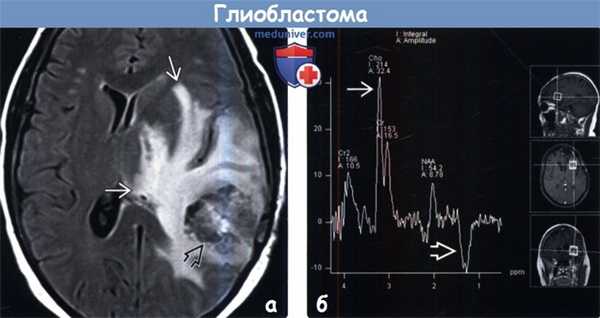

(а) МРТ, FLAIR, аксиальный срез: у пациента с МГБ определяется гетерогенное объемное образование и протяженная зона изменения сигнала вокруг него, что является признаком комбинации распространения клеток опухоли и вазогенного перифокального отека. С позиции патологии клетки опухоли обнаруживаются за пределами областей изменения сигнала.

(б) МР-спектроскопия: у пациента с рецидивирующей МГБ определяется классический МР-спектр, характерный для злокачественной опухоли, с выраженным подъемом пика холина (Cho), низким пиком NAA на 2,02 ppm и инвертированным пиком лактата на 1,33.